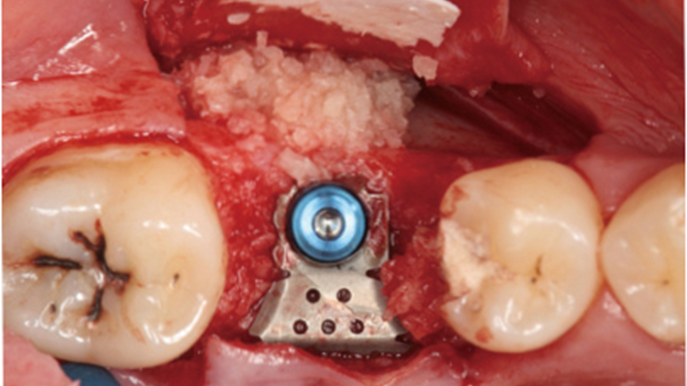

Clinical case: # 46 implant placement & GBR using i-Gen membrane for significant vertical resorption & mixed bone defect

- Courtesy of Dr. Iulian Filipov, Romania -

AnyRidge, mandibular posterior, i-Gen, resorption, bone defect, bone regeneration, space management, #46, GBR, Dr. Iulian Filipov

AnyRidge implant system, i-Gen